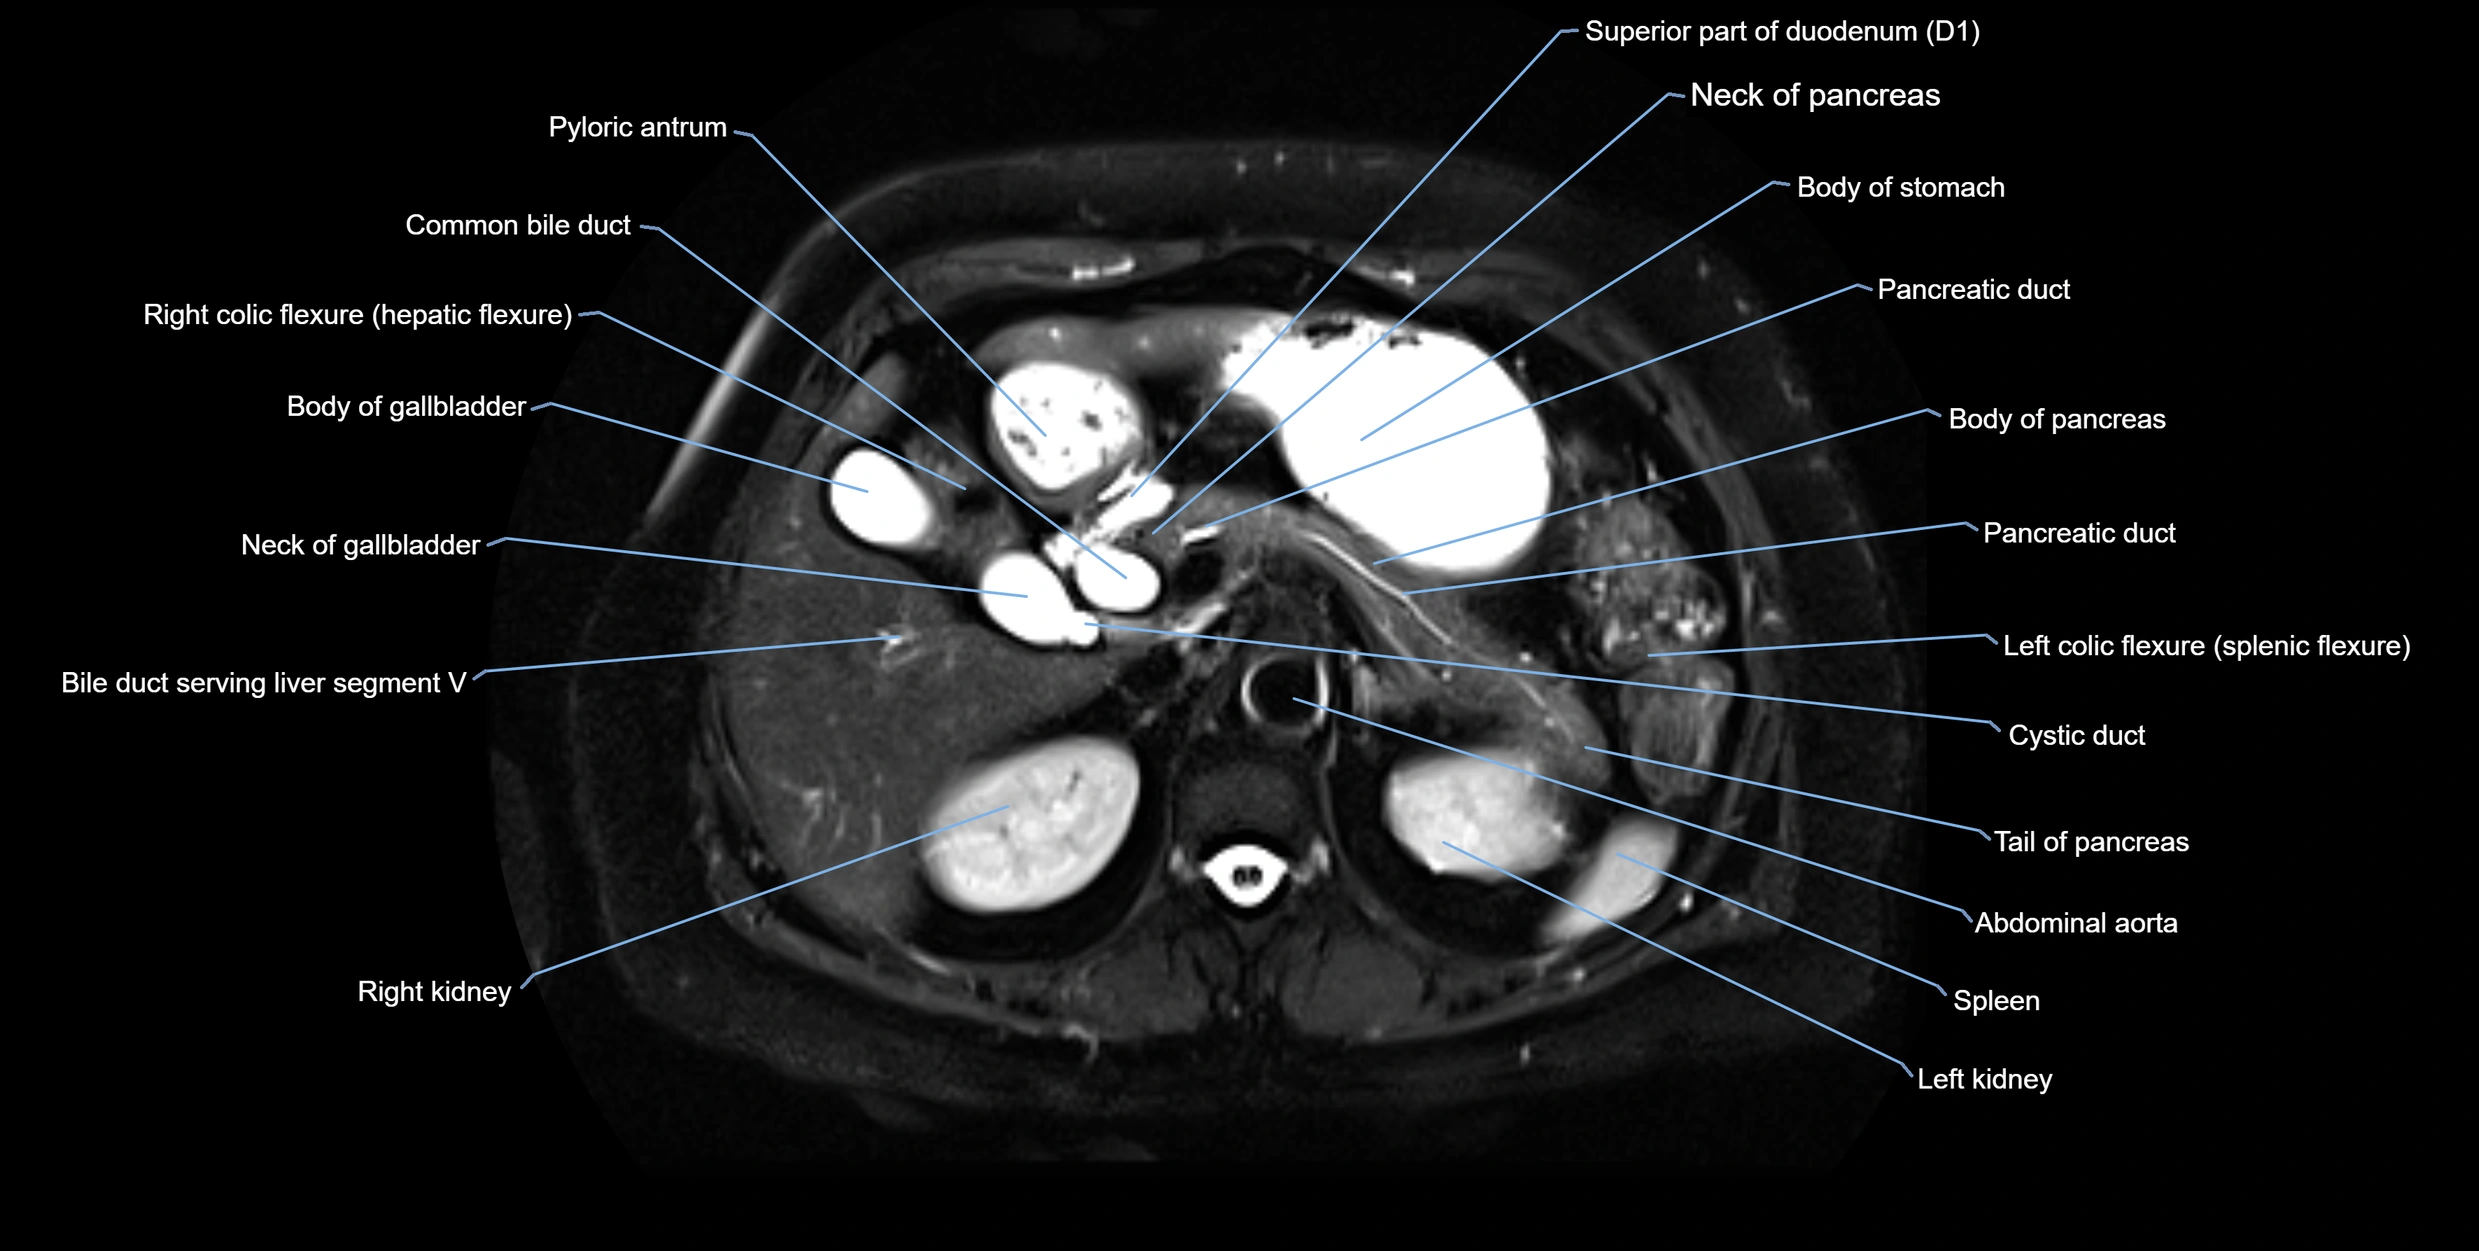

T2-weighted images:

• Duct fluid appears bright

• Accessory duct seen as a fine high-signal tubular structure in pancreatic head

T2 Fat-Saturated HASTE (single-shot):

• Accessory duct: bright, thin linear structure in pancreatic head

• Stones, strictures, or air bubbles appear as dark filling defects

• Excellent for rapid evaluation of duct patency

MRI image

image